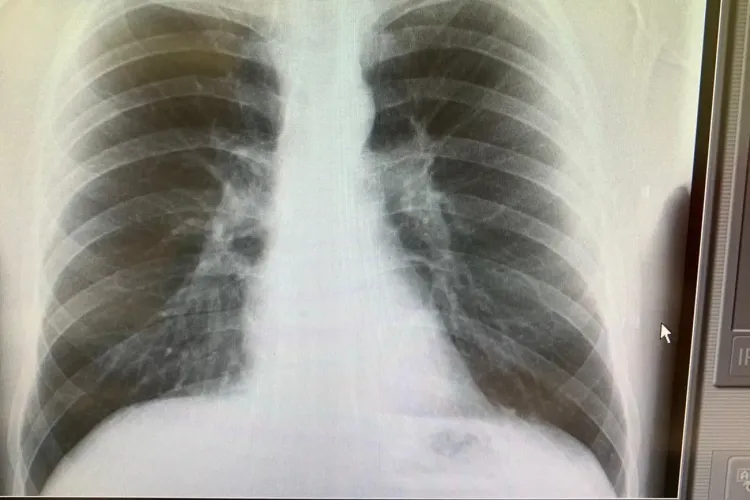

A murit Nelu Ploieşteanu. Cântărețul de muzică lăutărească era internat de două săptămâni la Spitalul Floreasca, după ce s-a îmbolnăvit de COVID

Nelu Ploieşteanu, unul dintre cei mai apreciaţi cântăreţi de muzică lăutărească, a murit vineri dimineaţă, din cauza complicaţiilor pe fondul Covid-19.

Cluj: Medic din prima linie către cei din stradă: Nu voi pleca urechea când medicii sunt transformați în asasini”

Un medic de la Spitalul Clinic de Boli Infecțioase Cluj susține că nu pleacă urechea la vorbele unora care îi fac pe medici asasini.